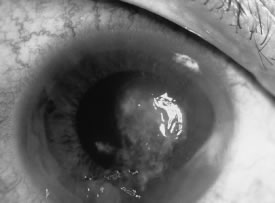

In the early stages of infection, filamentous fungi produce signs that are readily distinguishable from yeast or bacterial keratitis. The most distinctive sign is the presence of delicate, fine, feathery, opalescent, gray-white or yellow-white material in the anterior stroma, surrounded by scant cellular infiltrate or edema (Fig. 1). The epithelium may be intact. The overlying epithelium may be granular and the surface elevated and irregular in contour. Linear infiltrates typically extend into the adjacent stroma. Multiple discrete opacities may develop outside the perimeter of the principal focus of inflammation, either separated by clear stroma or linked by fine linear collections of inflammatory cells and material (Figs. 2 and 3). In the absence of inflammation in the adjacent stroma, branching hyphal fragments may be visualized by biomicroscopy (Figs. 4 and 5). Confocal microscopy may also detect hyphal elements within the stroma.28,29 Peripheral infection resembles noninfectious marginal infiltrative and ulcerative keratitis (Fig. 6). Multifocal keratitis may develop after contact lens wear or injury by multiple projectiles (Fig. 7). In the early stages, iritis is present and the intraocular pressure remains normal. Inappropriate, empirical therapy of fungal keratitis with topical fluoroquinolone or aminoglycoside antibiotics may suppress or eliminate the superficial elements but allow extension of the organisms into the stroma because these agents may possess selective antifungal activity.4,30,31

Fig. 1. Curvularia keratitis (slit-beam illumination). Note the fine feathery infiltrates extending from the central component, minimal cellular infiltrate in the adjacent stroma, and intact epithelium.